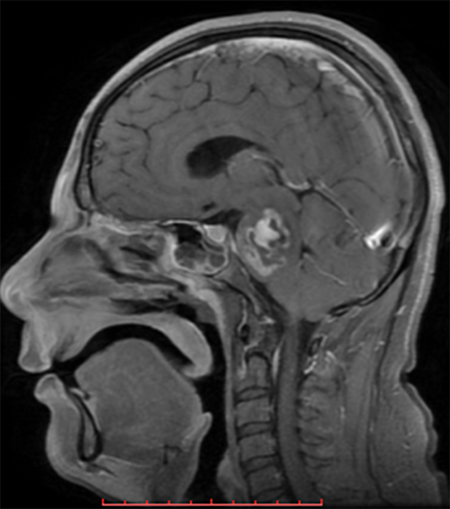

h.1) Resonancia magnética cerebral con corte sagital y secuencia T1 con gadolinio. Se encontró imagen heterogénea, con efecto de masa y zonas de reforzamiento en el interior. (Figura 1).

Figura 1. Resonancia magnética cerebral encorte sagital y secuencia T1 con gadolinio.